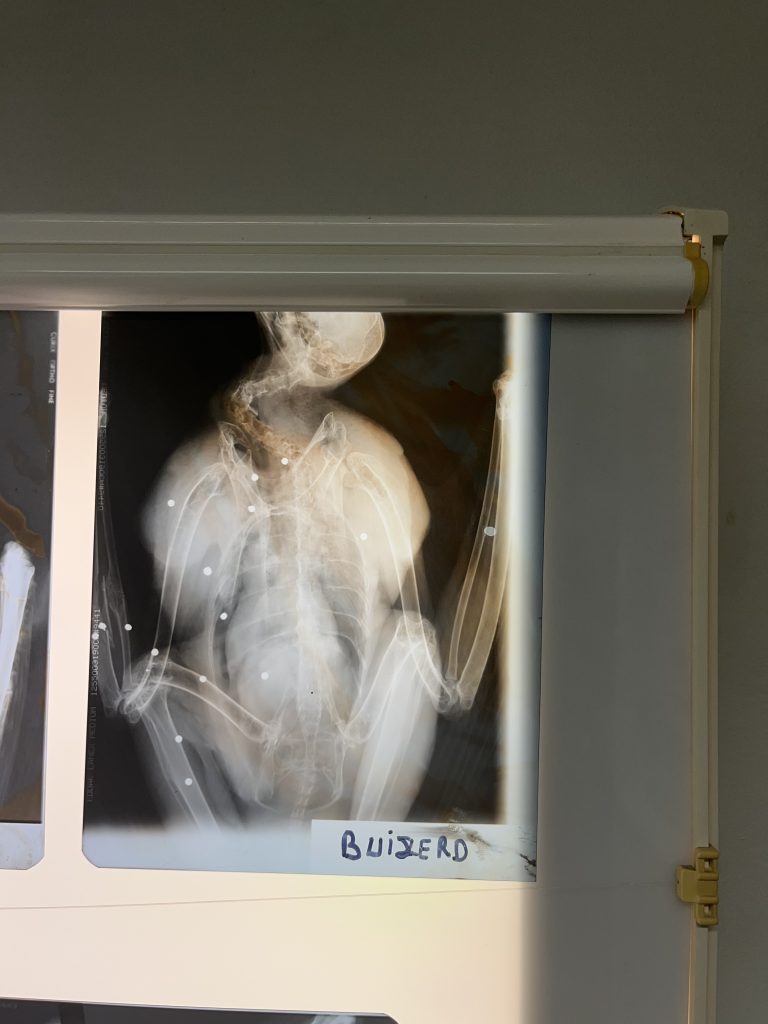

(Foto:Natuuhulpcentrum) Skuddskade på falk.

Dette er rømte eller konfiskerte rovfugler. Fugler født i fangenskap lærer seg aldri å jakte og vi vet heller ikke den genetiske bakgrunnen til fuglene, derfor kan de aldri slippes tilbake til naturen. Rovfugler kommer fra oppdrettere og selges til fugleshow og privatpersoner. Et problem er fugler som rømmer fra fugleshow, og de rømmer med tauet hengende etter seg og setter seg fast.